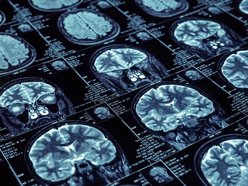

Standardem w diagnostyce guzów mózgu od lat pozostaje rezonans magnetyczny (MRI) z kontrastem. Choć niezwykle dokładny, ma on swoje ograniczenia – pokazuje strukturę tkanki i uszkodzenia bariery krew-mózg, ale nie zawsze oddaje pełną skalę „rozlania się” nowotworu.